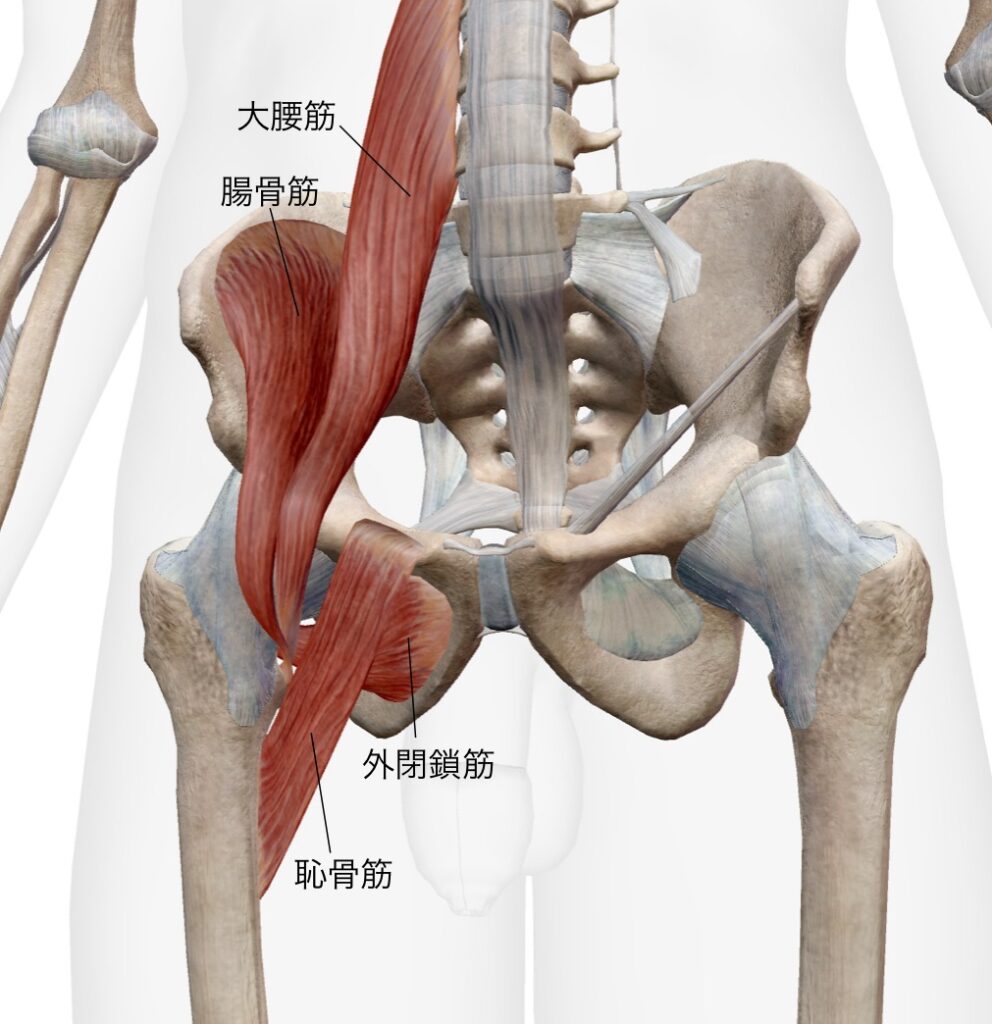

あくまでも一部ですが、写真のように股関節の周囲には様々な筋肉があります。

この外閉鎖筋、恥骨筋、腸腰筋が集まる部分がアプローチするポイントになります。